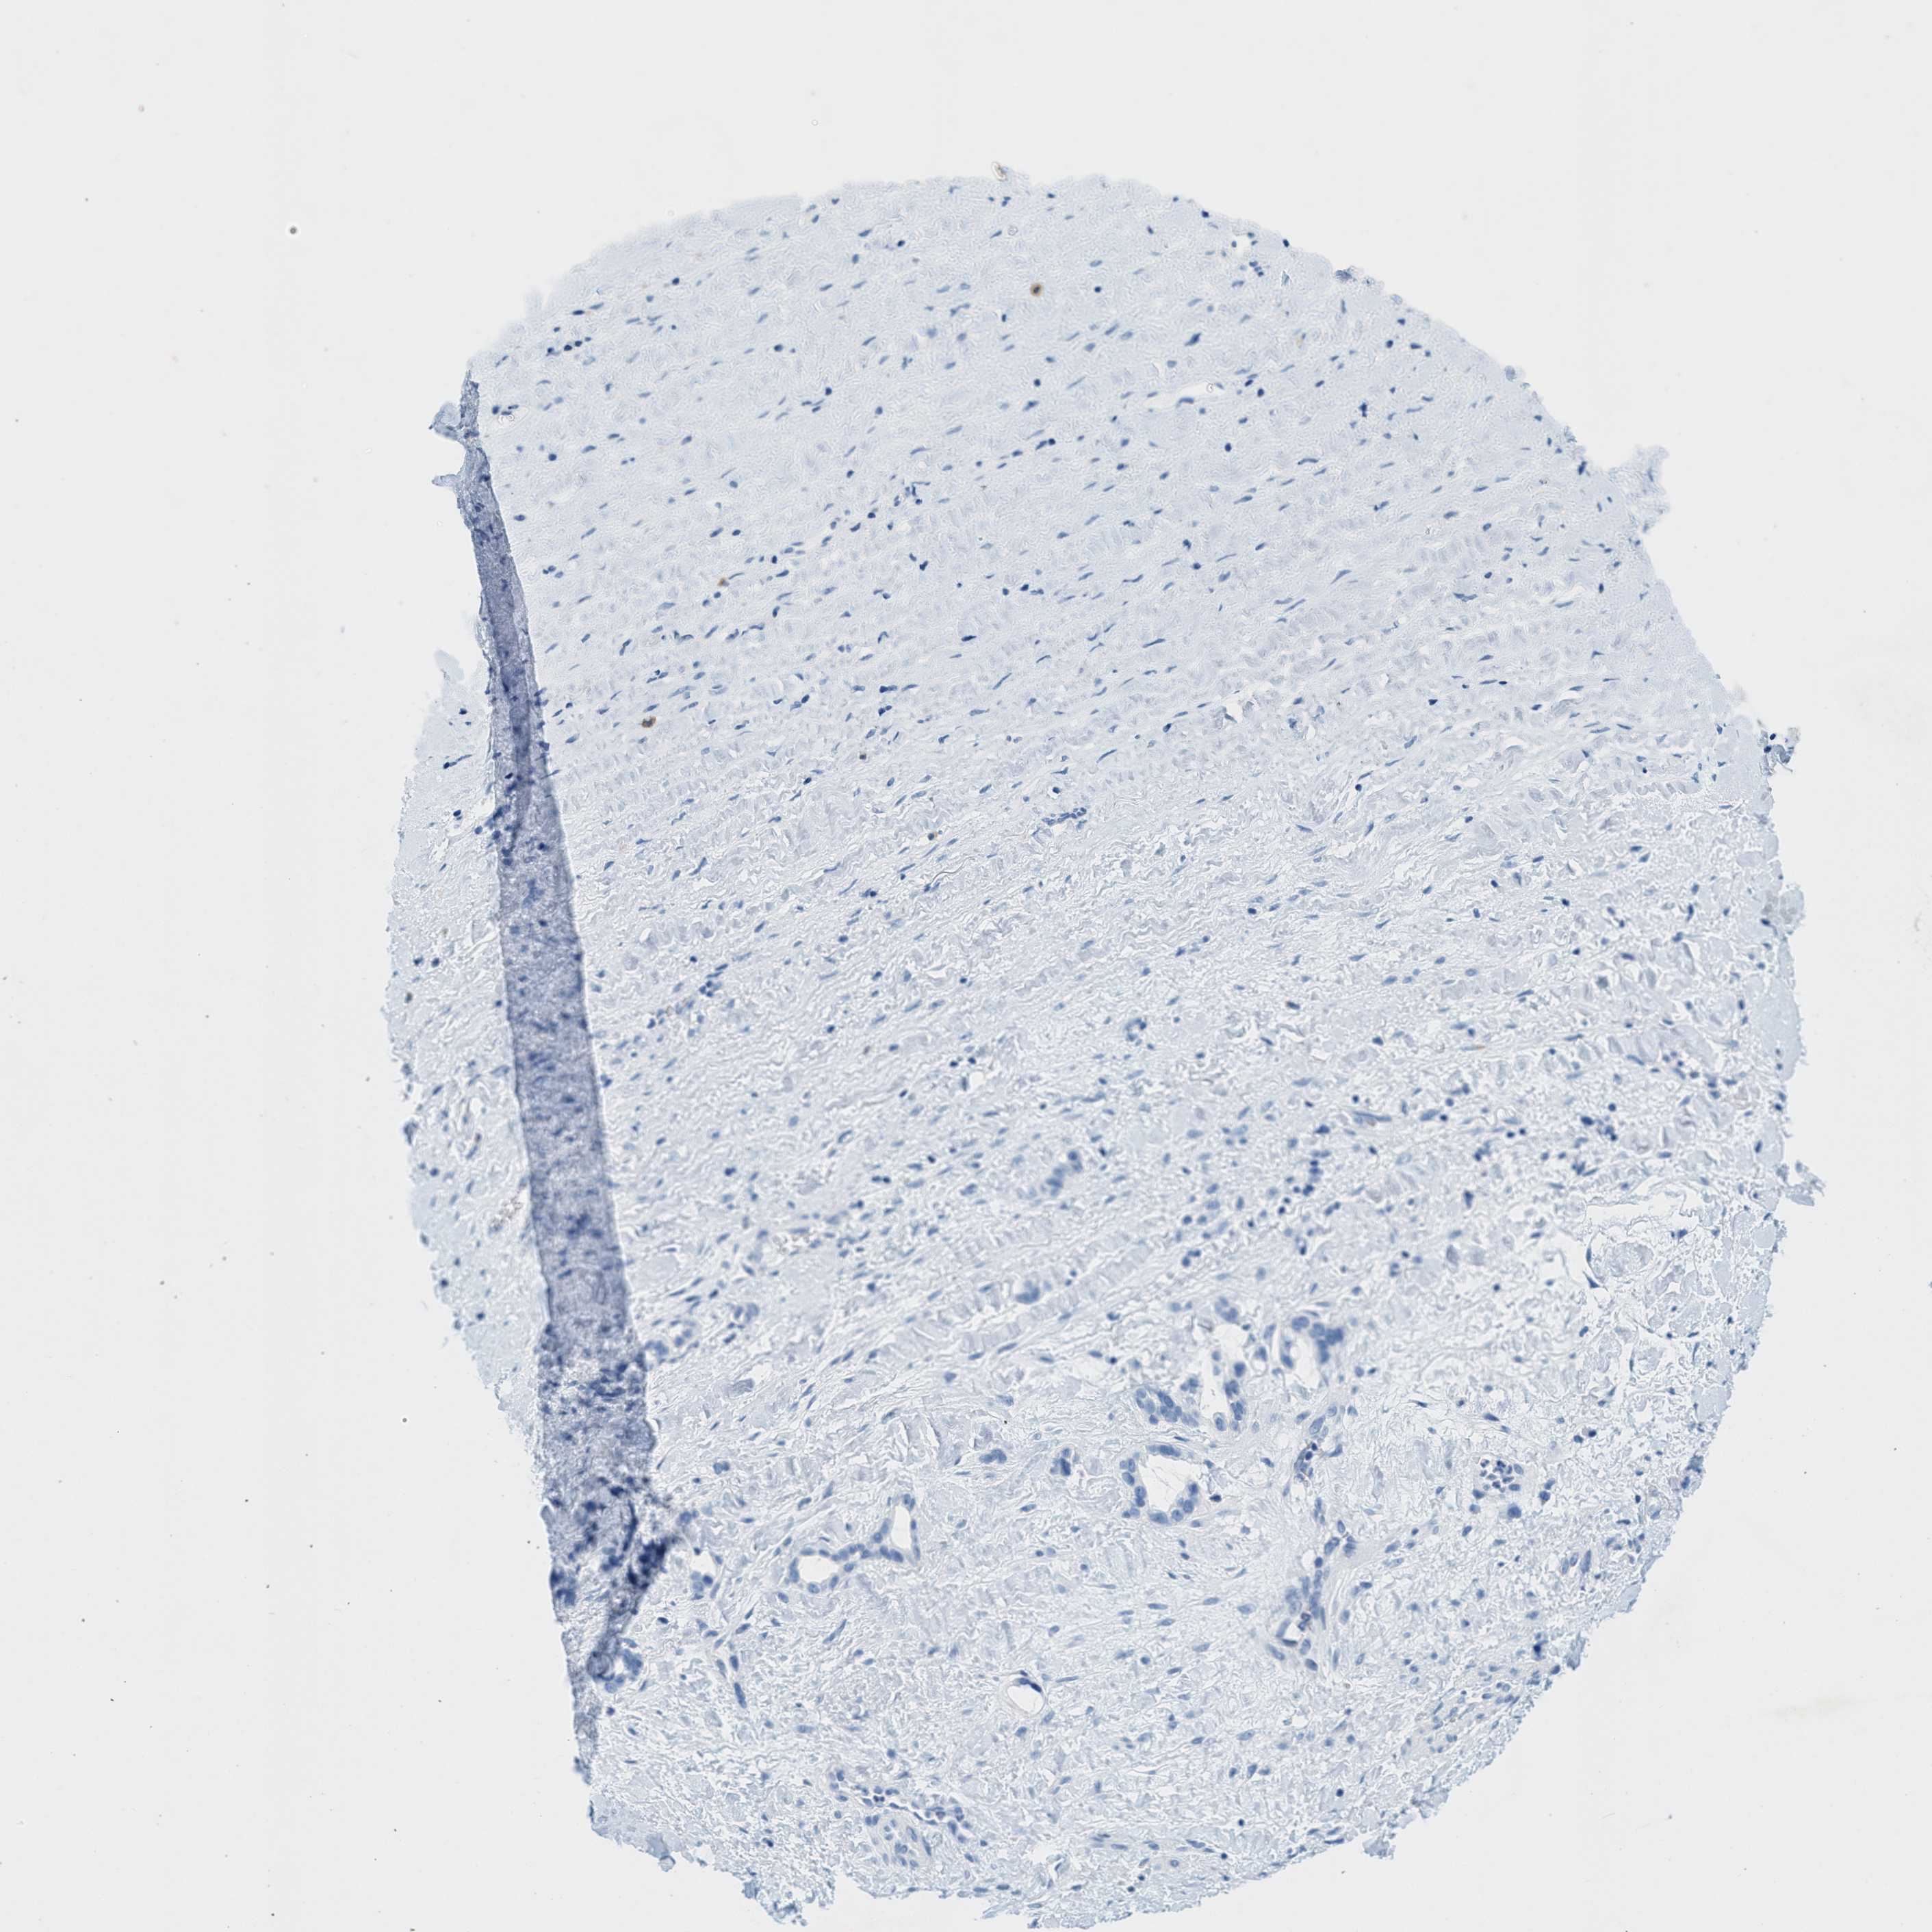

LIVER CANCER - Protein expressioni

A mouse-over function shows sample information and annotation data. Click on an image to view it in a full screen mode. Samples can be filtered based on level of antibody staining by selecting one or several of the following categories: high, medium, low and not detected. The assay and annotation is described here.

Note that samples used for immunohistochemistry by the Human Protein Atlas do not correspond to samples in the TCGA dataset.

Antibody stainingi

Antibody staining in the annotated cell types in the current human tissue is reported as not detected, low, medium, or high, based on conventional immunohistochemistry profiling in selected tissues. This score is based on the combination of the staining intensity and fraction of stained cells.

Each image is clickable and will lead to virtual microscopy that enables deeper exploration of all samples and also displays staining intensity scores, fraction scores and subcellular localization as well as patient and tissue information for each sample.

Antibody HPA017338

Staining

High

Medium

Low

Not detected

Intensity

Strong

Moderate

Weak

Negative

Quantity

>75%

75%-25%

<25%

None

Location

Nuclear

Cytoplasmic/membranous

Cytoplasmic/membranous,nuclear

Carcinoma, Hepatocellular, NOS

Cholangiocarcinoma